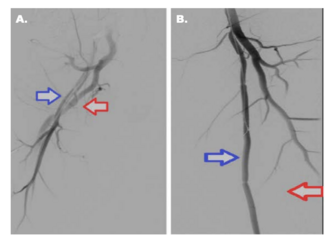

This case report describes arterial recoiling as an indication for stent placement in a case of symptomatic FMD affecting the right external iliac artery.